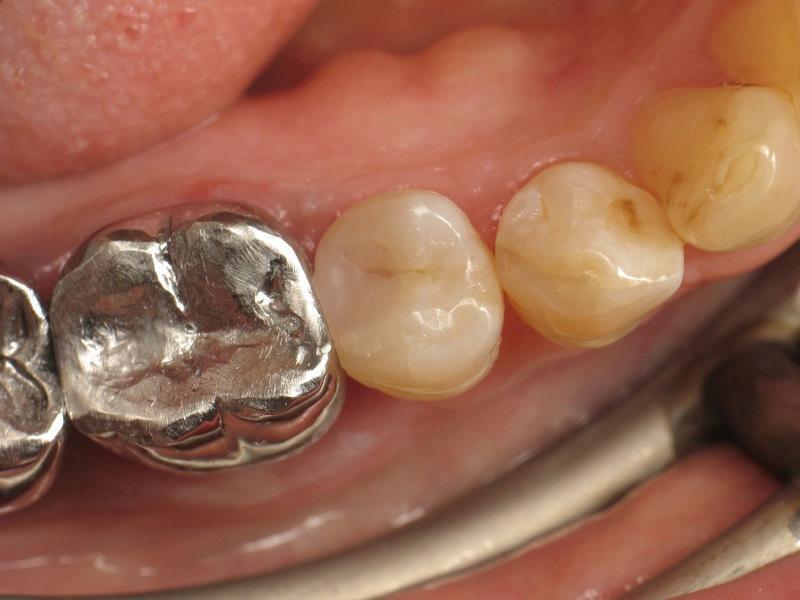

Фото 2: Наложение коффердама.